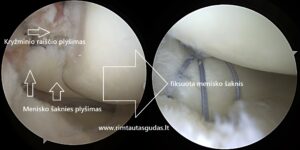

Meniskų susiuvimai, rekonstrukcijos, implantacijos ir transplantacijos.